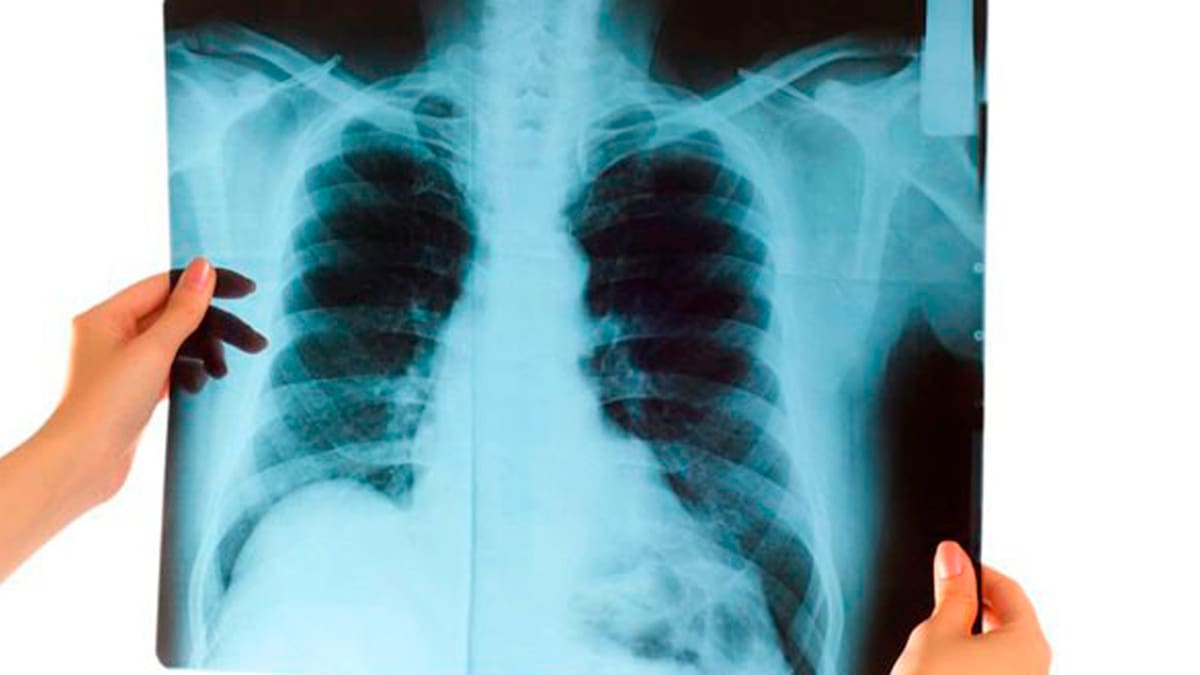

En Colombia las cifras también son representativas, de acuerdo el Ministerio de Salud y Protección Social, 34.800 personas mueren anualmente por enfermedades asociadas al consumo del tabaco, 3.076 son causadas por los cánceres de tráquea, bronquios y pulmón, y en mayor prevalencia 4.584 muertes son causadas por las enfermedades crónicas de las vías respiratorias, entre ellas la enfermedad pulmonar obstructiva crónica (EPOC).

Precisamente con respecto al EPOC, la Nueva EPS durante el 2020 identificó 52.219 afiliados con esta patología, la mayor concentración de los pacientes se encuentra en las ciudades del Bogotá, Cali, Medellín y Barranquilla.

Esta enfermedad se caracteriza por un bloqueo persistente del flujo de aire. Los síntomas más frecuentes son la disnea (falta de aire), la expectoración anormal y la tos crónica.

A medida que la enfermedad empeora, pueden hacerse muy difíciles actividades cotidianas como subir unos cuantos escalones o llevar una maleta.

Su presencia se confirma con una prueba diagnóstica, llamada espirometría, que mide la cantidad y la velocidad del aire inspirado y espirado. Como tiene una evolución lenta, generalmente se diagnostica en personas de 40 años o más.

El EPOC no se cura y es esencial dejar de fumar para prevenir la progresión de la enfermedad. Existen varios tratamientos que pueden ayudar a controlar sus síntomas y a mejorar la calidad de vida de los pacientes. Por ejemplo, los medicamentos broncodilatadores pueden mejorar la disnea.